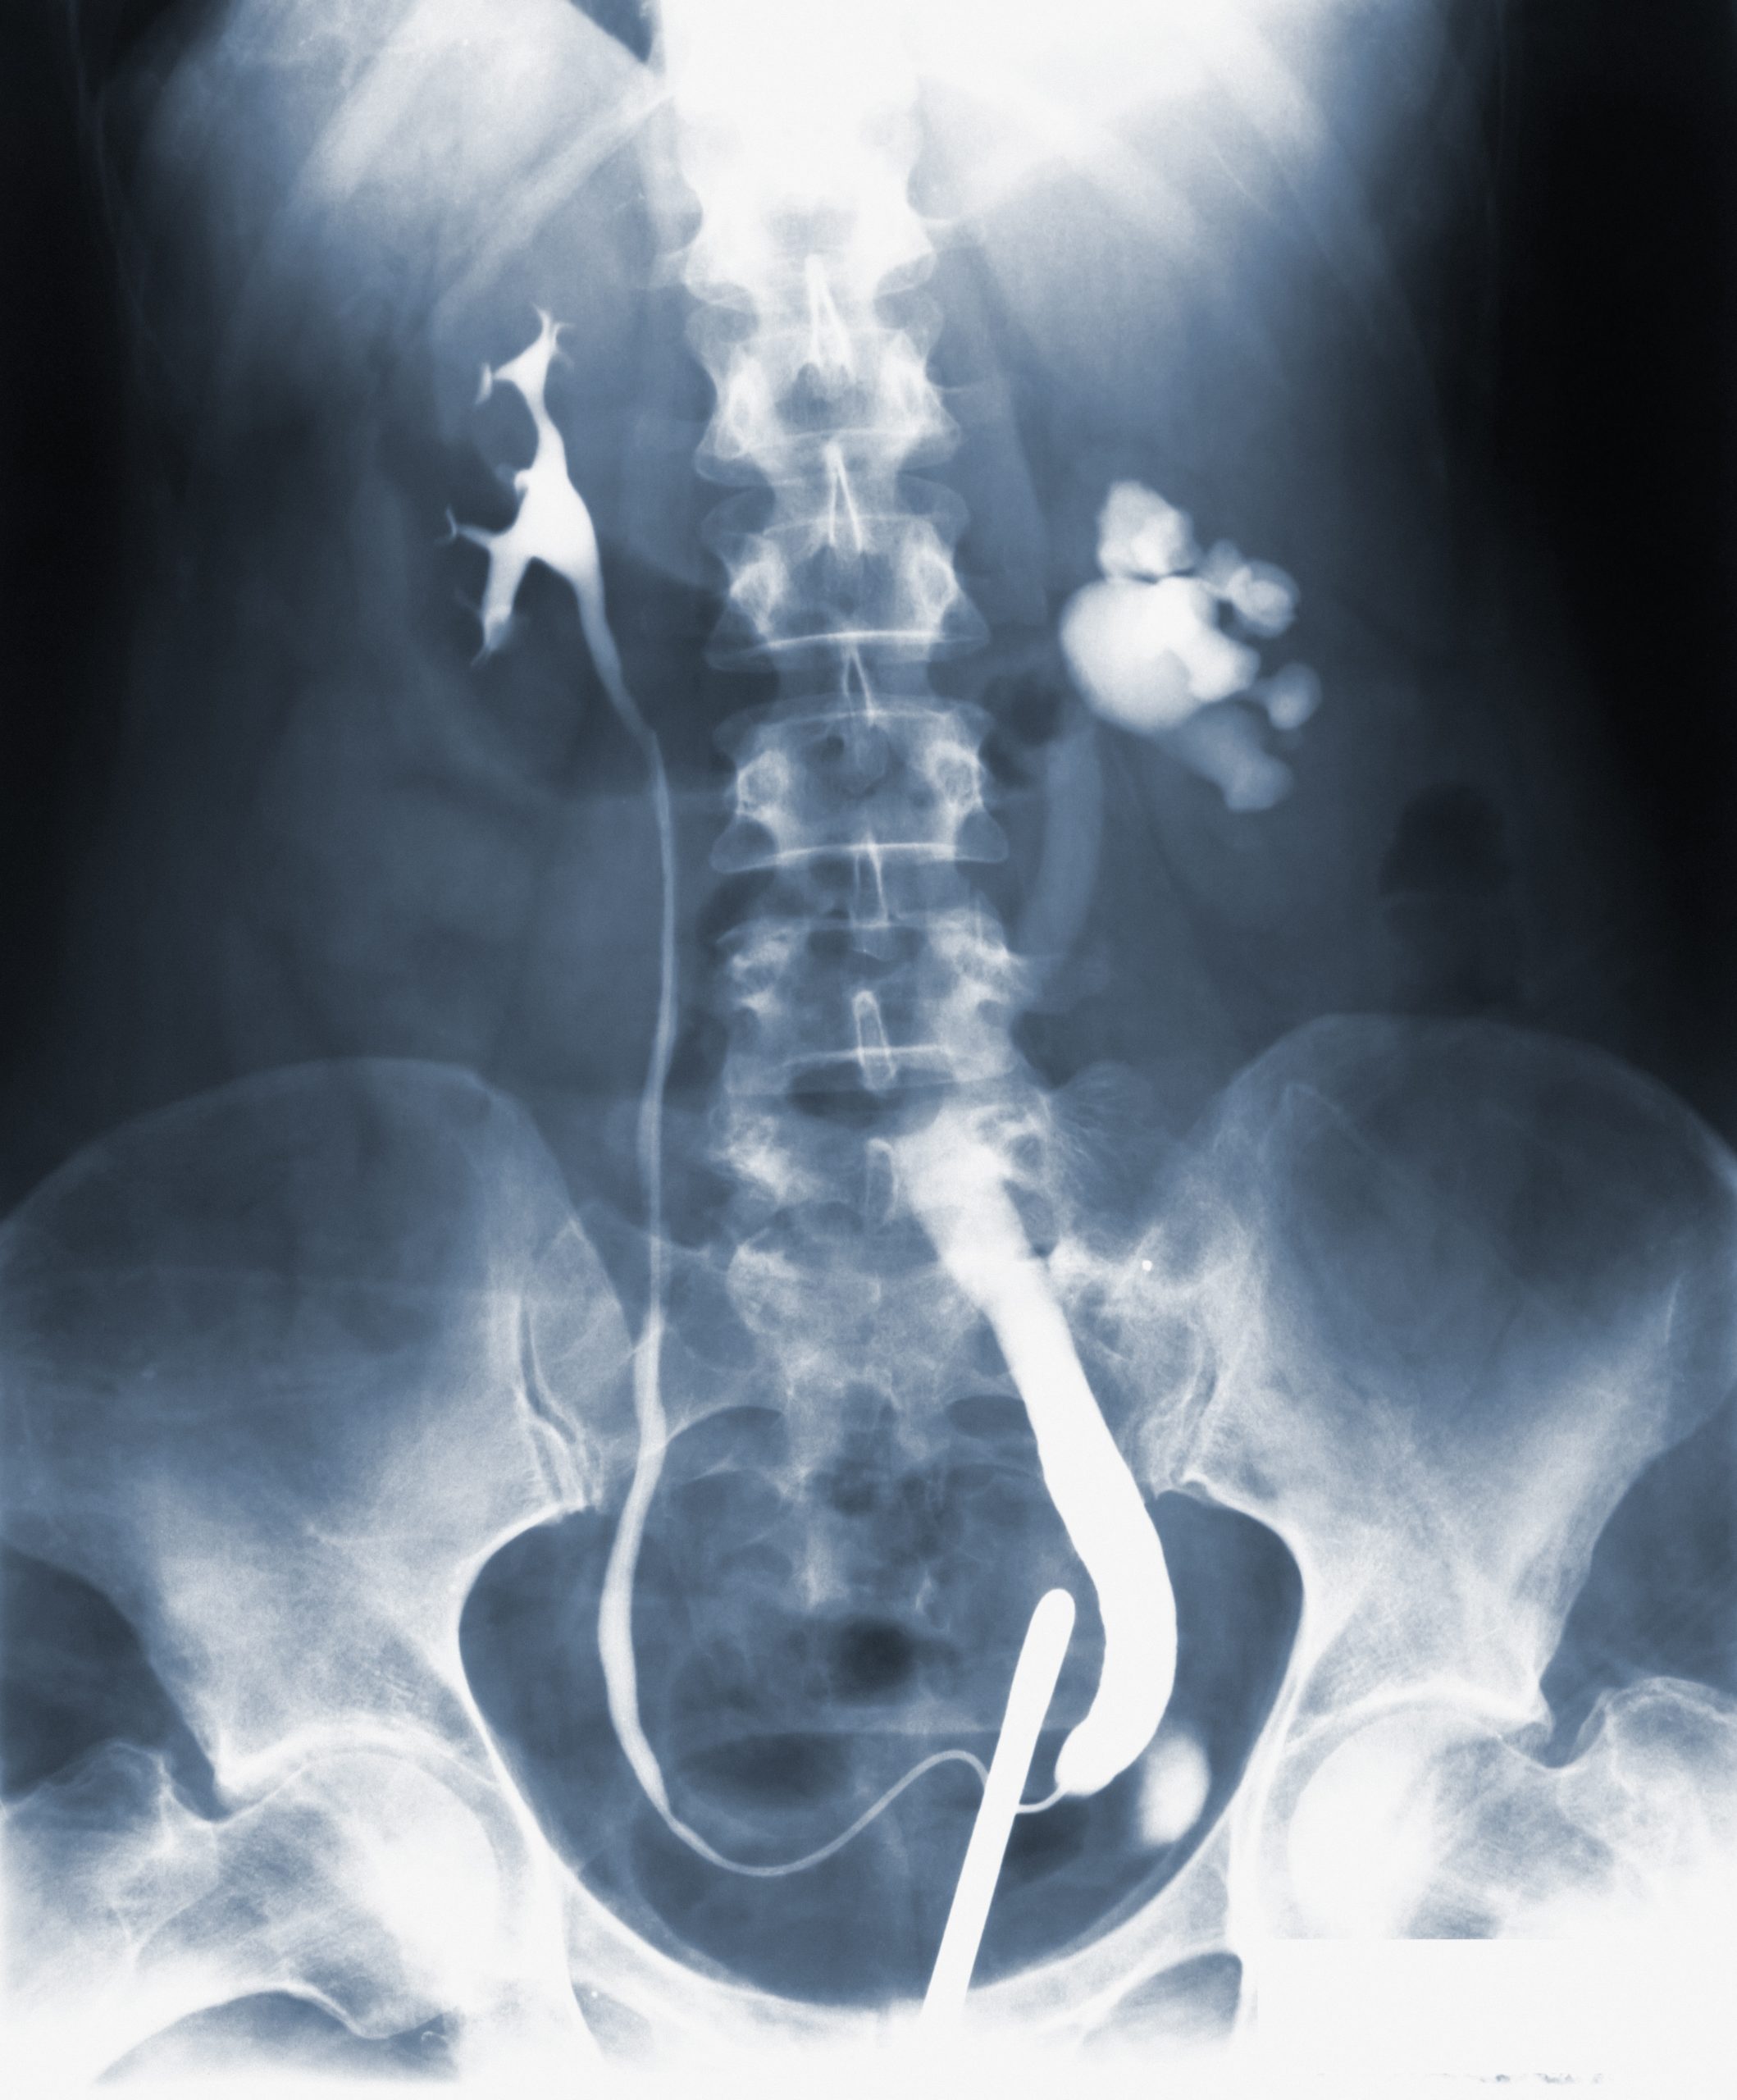

Knowing your family history of colorectal cancer can help you understand your risk of developing the disease and take steps to prevent it. If you have a family history of colorectal cancer or an inherited condition that increases your risk, your doctor may recommend starting screening earlier or undergoing more frequent screening. Screening tests, such as colonoscopies, can help detect precancerous polyps or early-stage cancer when it’s easier to treat.